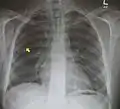

Pneumomediastinum with angel wing sign[14]